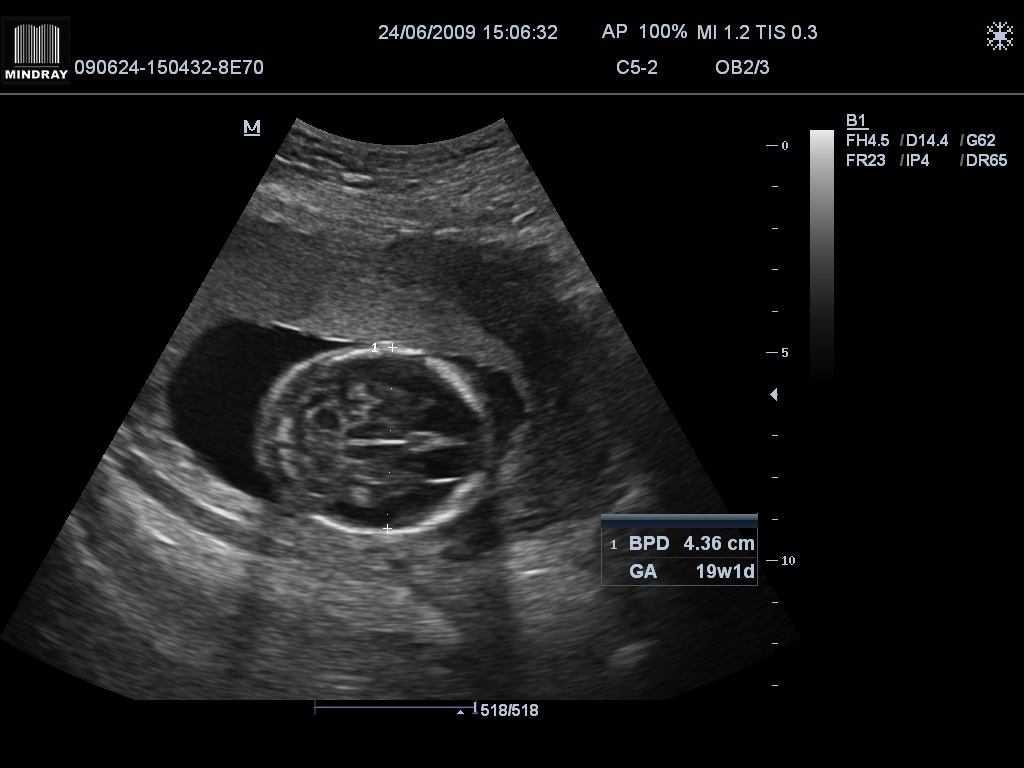

УЗИ в 19 недель беременности — что нового узнают будущие родители?

Экватор беременности - время, когда будущий малыш почти полностью формируется как маленький человечек. УЗИ на этом сроке проводится, как правило, от 17 до 20...